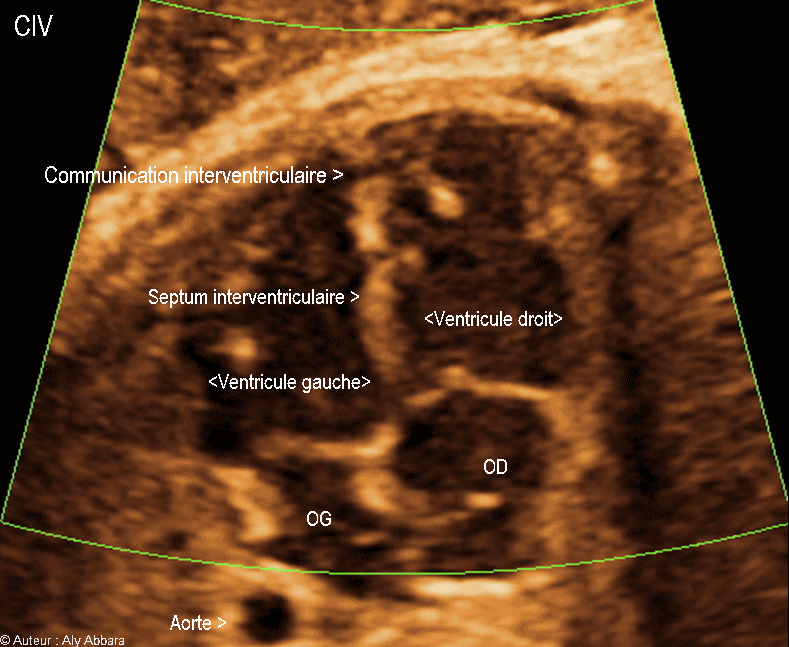

Vidéo et image animée échographiques cardiaques avec Doppler-couleur montrant une malformation cardiaque congénitale isolée ; il s'agit d'une communication interventriculaire (CIV) musculaire, trabéculée et apicale.

Cette CIV musculaire apicale est de moins de 3 mm de largeur, située à l'extrême pointe de ventricule gauche, isolée, sans autre anomalie morphologique ou fonctionnelle cardiaque décelée lors de cette examen.

Le Doppler couleur montre un flux sanguin bidirectionnel sur cette communication interventriculaire apicale.

Fœtus âgé de 33 SA.

On voit bien une CIV musculaire apicale de moins de 3 mm à l'extrême pointe de ventricule gauche.